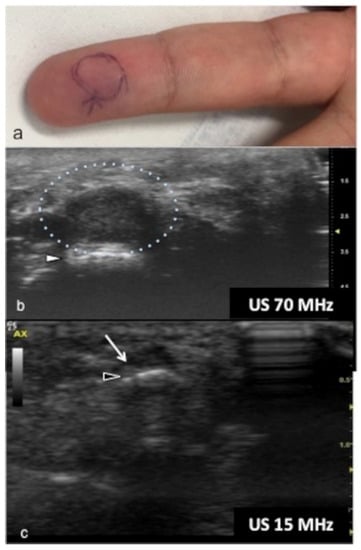

Figure 11.

Glomus tumor. The location corresponds to the pulp of finger IV (a). The patient had the classical triad of symptoms: paroxysmal pain, pinpoint pain, and cold hypersensitivity, lasting for two years. In (b), UHFUS shows a well-delimited nodule in contact with the adjacent phalangeal bone (arrowhead), but no cortical deformity is present. No significant hyperemia on color Doppler was noticed. On CUS (c), the nodule was delineated only thanks to the help of the preliminary UHFUS exam.

Figure 12.

Glomus tumor in the subungual space. No clear alterations were visible during clinical examination at the site of pain (circle in (a)). In (b), UHFUS effectively demonstrates the presence of a hypo-isoechogenic nodule (calibers) in contact with the adjacent phalangeal bone (arrowhead) under the nail plate (arrows). Note the small deformation of the nail plate. Mild vascularization on color Doppler was present (c).

Glomus tumors are rare, benign, vascular neoplasms arising from the glomus body, which is a contractile neuromyoarterial structure found in the reticular dermis. This structure controls blood pressure and temperature by regulating blood flow in the cutaneous vasculature. Hyperplasia in any of these parts can lead to tumor formation, which is extremely painful. Glomus tumors account for 1–5% of soft-tissue tumors of the hand, and 75% of them are subungual in location. Other less commonly involved sites in the hand are the nail matrix, nail bed, and pulp of the finger. The delay in diagnosing these tumors for many years is a significant problem. It is not uncommon that patients are easily misdiagnosed with conditions such as neuropathic complaints, arthritis, or neuralgia and undergo unsuitable treatment. For these reasons, when the clinical examination is equivocal, noninvasive imaging techniques may be needed to aid in the diagnosis and delineate the anatomy preoperatively. Complete surgical excision of the tumor is the only effective treatment. Incomplete excision is considered the main cause of recurrence. US follow-up and/or intraoperative US may be useful for reducing recurrence and ensuring adequate resection, and the UHFUS tool is promising in this field [56].